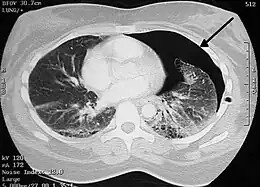

Chest X-ray

A plain chest radiograph, ideally with the X-ray beams being projected from the back (posteroanterior, or "PA"), and during maximal inspiration (holding one's breath), is the most appropriate first investigation.[32] It is not believed that routinely taking images during expiration would confer any benefit.[33] Still, they may be useful in the detection of a pneumothorax when clinical suspicion is high but yet an inspiratory radiograph appears normal.[34] Also, if the PA X-ray does not show a pneumothorax but there is a strong suspicion of one, lateral X-rays (with beams projecting from the side) may be performed, but this is not routine practice.[15][19]

Chest X-ray showing a pneumothorax on the right (left in the image), where the absence of lung markings indicates that there is free air inside the chest

It is not unusual for the mediastinum (the structure between the lungs that contains the heart, great blood vessels, and large airways) to be shifted away from the affected lung due to the pressure differences. This is not equivalent to a tension pneumothorax, which is determined mainly by the constellation of symptoms, hypoxia, and shock.[13]

The size of the pneumothorax (i.e. the volume of air in the pleural space) can be determined with a reasonable degree of accuracy by measuring the distance between the chest wall and the lung. This is relevant to treatment, as smaller pneumothoraces may be managed differently. An air rim of 2 cm means that the pneumothorax occupies about 50% of the hemithorax.[15] British professional guidelines have traditionally stated that the measurement should be performed at the level of the hilum (where blood vessels and airways enter the lung) with 2 cm as the cutoff,[15] while American guidelines state that the measurement should be done at the apex (top) of the lung with 3 cm differentiating between a "small" and a "large" pneumothorax.[35] The latter method may overestimate the size of a pneumothorax if it is located mainly at the apex, which is a common occurrence.[15] The various methods correlate poorly but are the best easily available ways of estimating pneumothorax size.[15][19] CT scanning (see below) can provide a more accurate determination of the size of the pneumothorax, but its routine use in this setting is not recommended.[35]

Not all pneumothoraces are uniform; some only form a pocket of air in a particular place in the chest.[15] Small amounts of fluid may be noted on the chest X-ray (hydropneumothorax); this may be blood (hemopneumothorax).[13] In some cases, the only significant abnormality may be the "deep sulcus sign", in which the normally small space between the chest wall and the diaphragm appears enlarged due to the abnormal presence of fluid.[16]